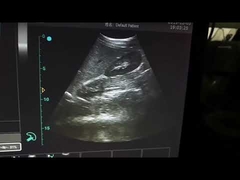

Kalite Portatif Ultrason tarayıcı, taşınabilir ultrason tarayıcı manufacturer from China